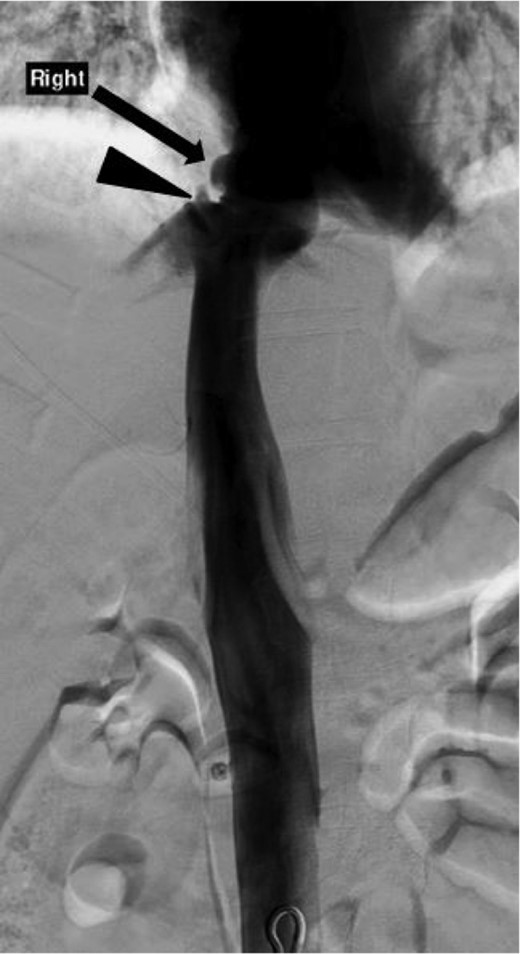

The patient remained in stable hemodynamic condition over the subsequent 3 h, and the decision was made to obtain an IVC venogram, depicted in Fig. 6, which showed a small focal contour irregularity of the suprahepatic IVC and slight irregularity of the right middle vein consistent with a pseudoaneurysm and no active contrast extravasation. Conservative management of the hepatic laceration and IVC injury was continued in the intensive care unit with strict bed rest. On post trauma day 3, her tibia and fibula fractures were repaired without complications. The patient was discharged on post trauma day 7.

Inferior venacavagram showing a mild contour irregularity of the suprahepatic IVC without contrast extravasation (arrow) and a slight contour irregularity of the middle hepatic vein without contrast extravasation (arrowhead) consistent with a pseudoaneurysm of the IVC and right middle hepatic vein.